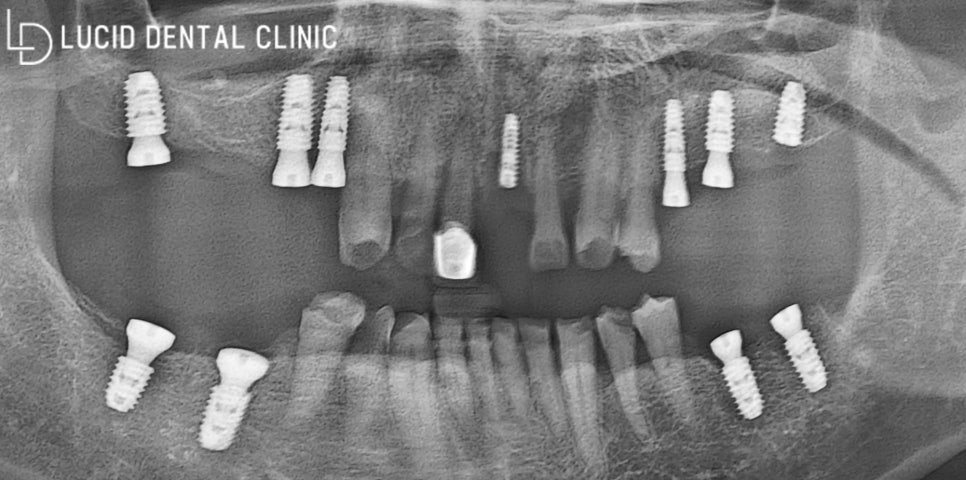

약속한 당일이 되고, 마취와 함께

본격적인 치료를 시작해 봤는데요.

먼저 문제가 되는 치아를 모두 발거하고,

소독과 세척을 반복해서 시행했습니다.

혹시 모를 감염이 발생하지 않도록

꼼꼼하게 시행하는 것이 중요합니다!

이제 아까 말씀드렸던

디지털 분석 가이드를

이용할 차례인데요.

미리 모의 식립을 진행하여

식립 위치를 파악할 수 있어

훨씬 안정되고 정밀하게

시행할 수 있다는 장점이 있죠.

곧바로 제작된 가이드를 이용하여

위치에 맞게 픽스처를 즉시 식립했는데요.

적당한 치은 형태를 만들어 줄 수 있도록

어버트먼트를 체결하며 마무리했습니다.

이대로 가면 식사하실 때 불편할 수 있으니

임시 치아를 만들어 씌워 드렸는데요.

이제 이 상태로 치은과 치조골이

온전히 회복되길 기다려야 됩니다.